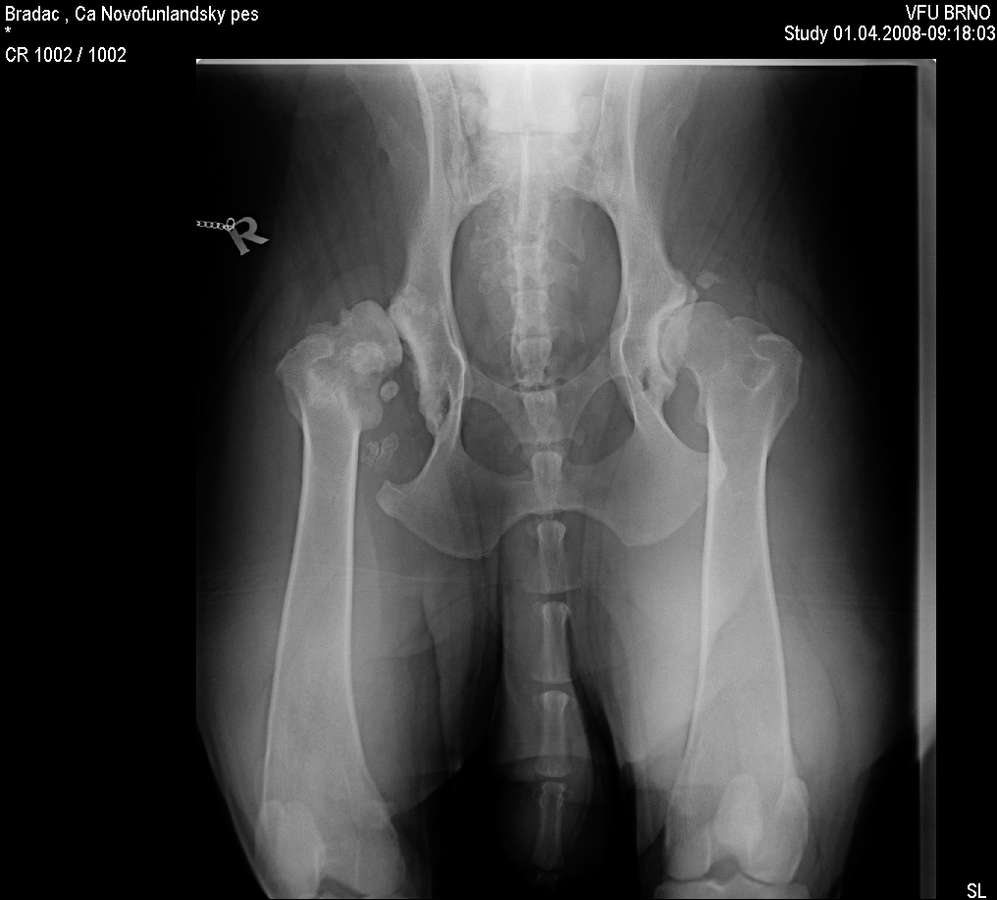

Novofundlanďan Grif (v PP má Lancaster Triladé) přestal chodit v osmi měsících. Diagnóza zněla: dysplazie kyčelních kloubů, na pravém kyčelním kloubu luxace, na levém subluxace. Tedy česky: Levý kyčel má povysunutý kloub z jamky, pravý je venku. Doktor z renomované brněnské kliniky zkusil doporučit uspání: "ten pes vám nikdy nebude plnit to, k čemu jste si ho pořizovali" Jak moc se mýlil ukázal až čas. Odmítl jsem to tehdy vzdát bez boje a jeli jsme s rentgeny na doporučení k MVDr. Novákovi, který Grifovi píchl přímo do kloubu vysokomolekulární hyaluronovou kyselinu, doporučil další léky (Caniviton, Omega3 - Pupalkový olej, ), měsíc klid a uvidíme.

Znovu na rentgenu jsme byli ve zhruba čtyřech letech, kdy Grif prodělal amputaci plovací blány, protože se mu po zánětu udělala boule velikosti velkého vlašského ořechu. Rentgen, který zde vidíte je poslední, ze skoro sedmi let, kdy jsme byli na operaci s předním loktem, artrózu bylo nutné odfrézovat. Ano, to byla poslední zatím neoperovaná noha. Pro přehled je vedle další rentgen zdravého psa (mladého leonbergera). Prohlédněte si oba klouby. (Kliknutím otevřete obrázky v plné velikosti).